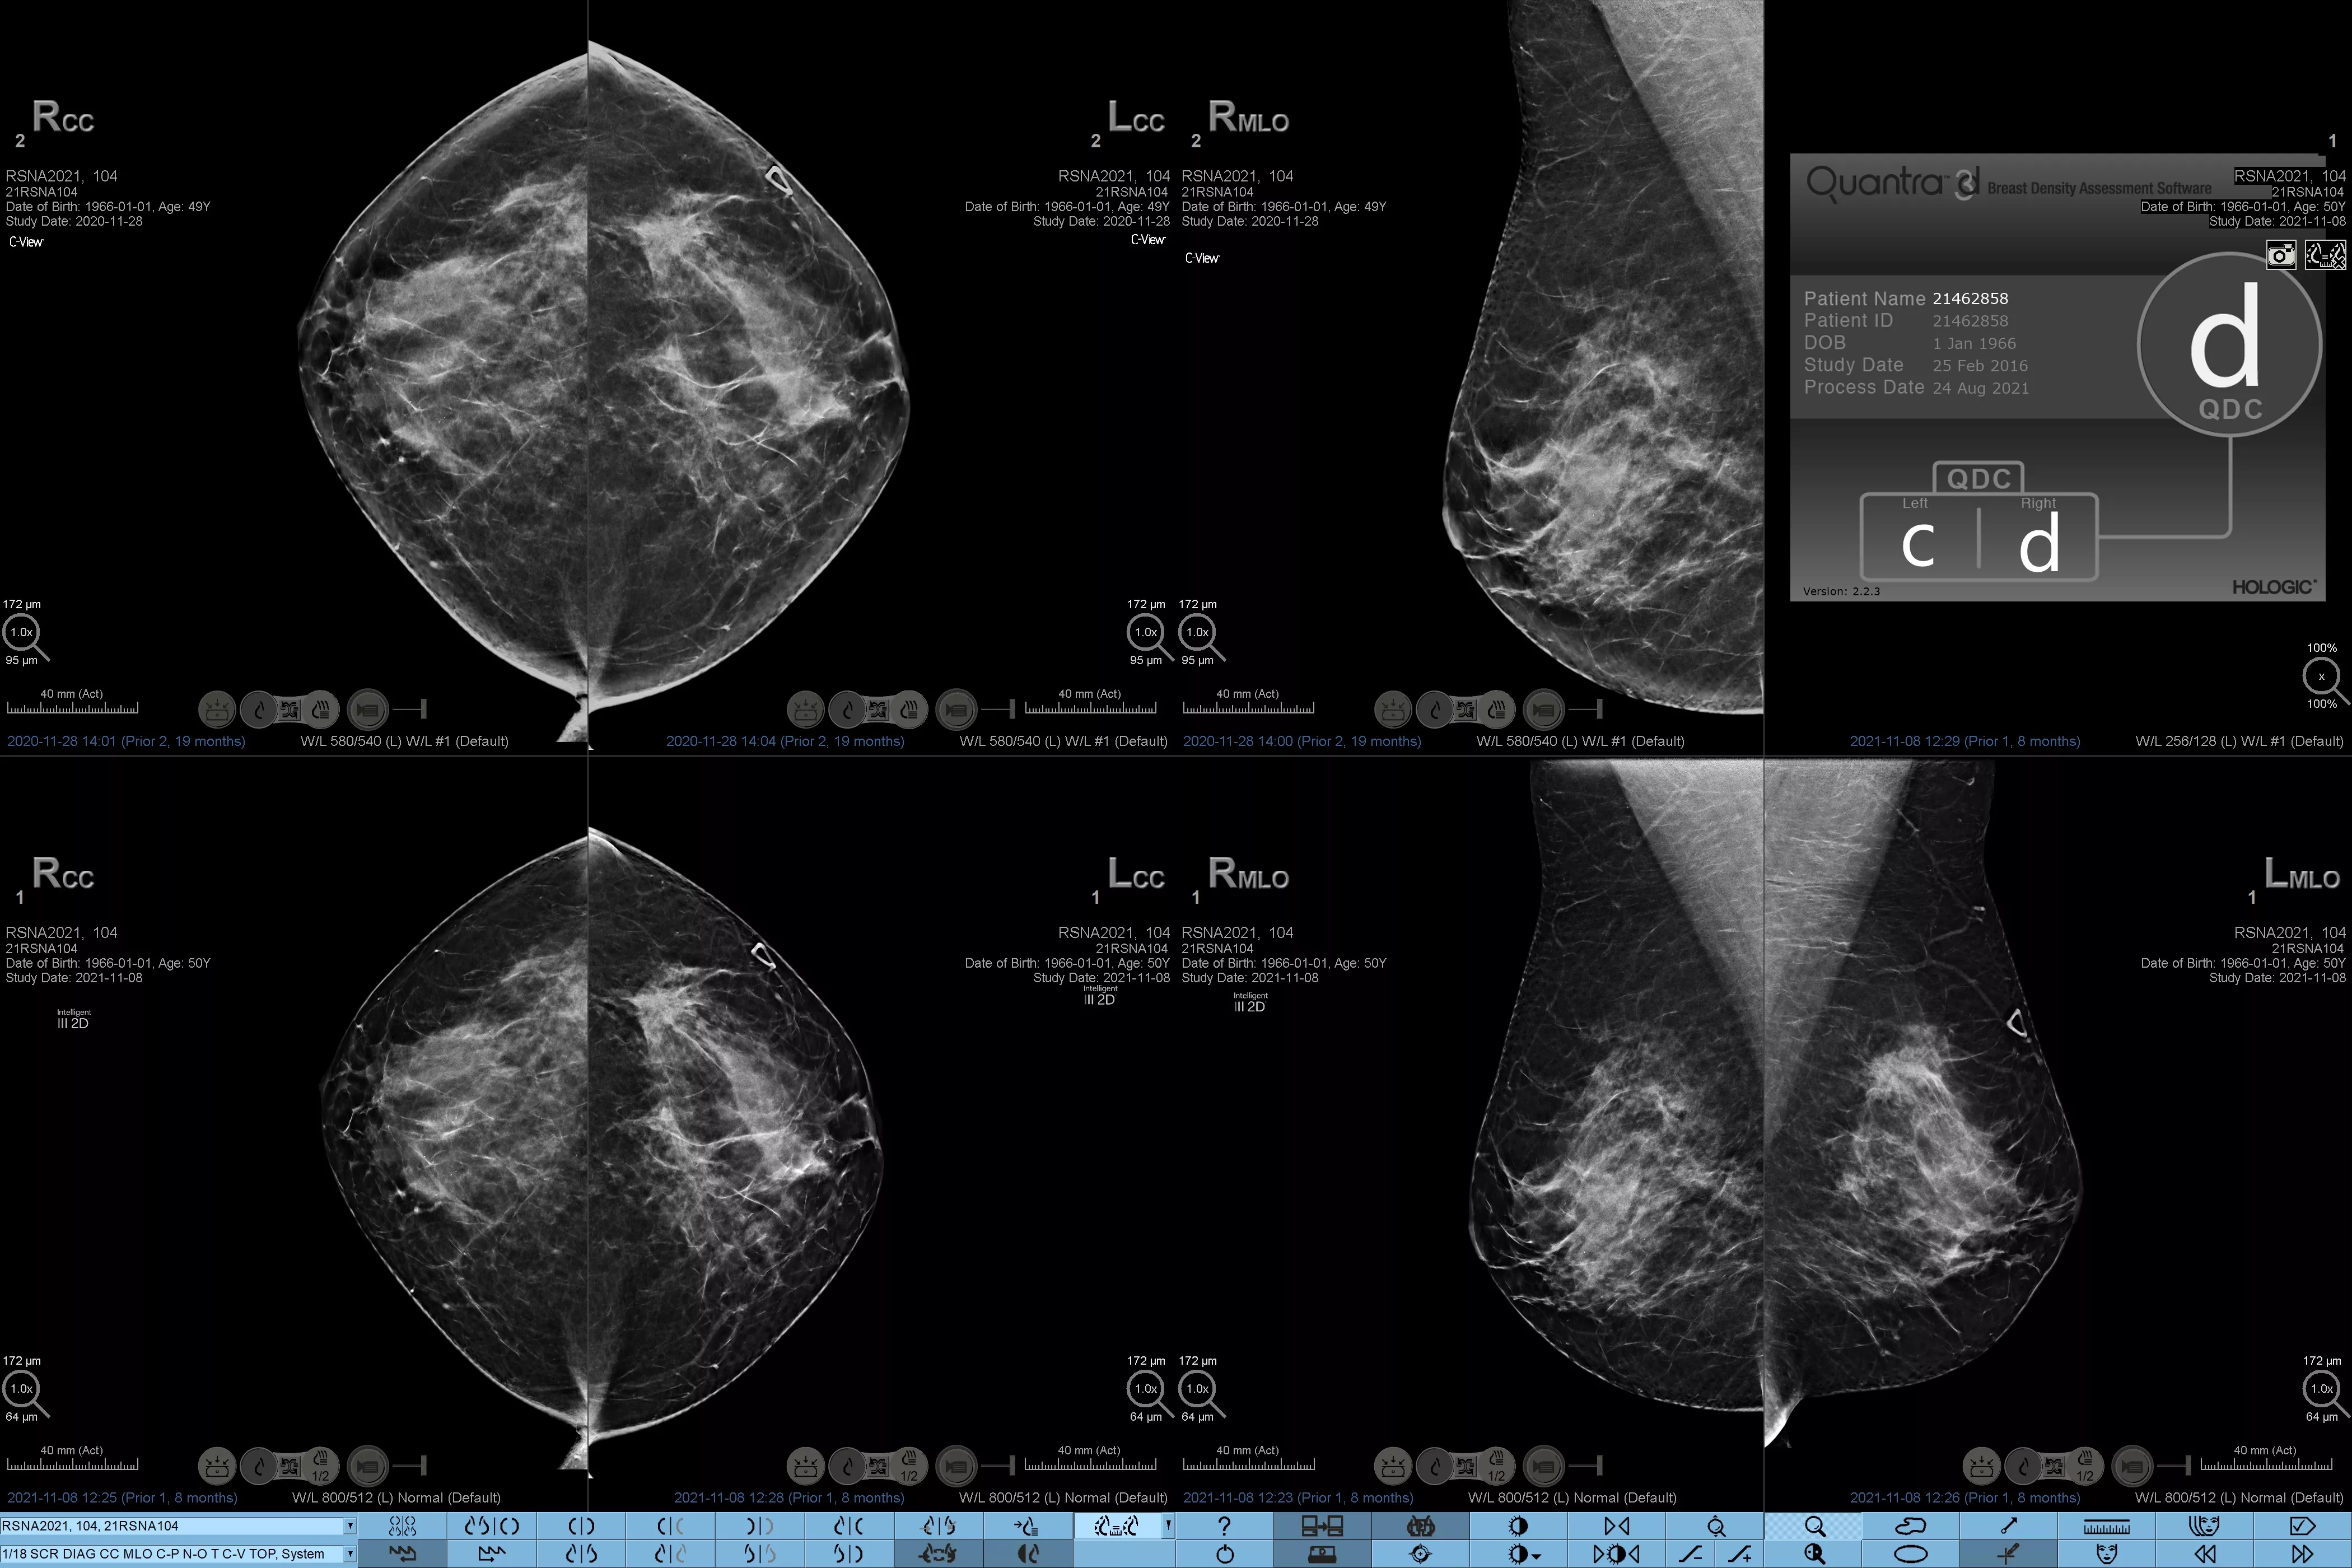

乳腺密度分析の標準化

乳腺濃度が高いと、女性の乳がんリスクが高まることが知られています1。したがって、正確でバイアスのない分析が極めて重要です。機械学習を活用する Quantra テクノロジーソフトウェアは、2D™ 画像とトモシンセシス画像の両方を分析して乳腺密度の割合を分類します。米国放射線医学会 (ACR) BI-RADS アトラス第 5 版のガイドラインに従って、乳房を 4 つの乳房組成のカテゴリーに分類します2

乳房組織の質感とパターンの分析に基づいて乳腺密度のカテゴリーを割り当てる客観的な機械学習アルゴリズム。

*スコアは、米国放射線学会 (ACR) BI-RADS アトラス第 5 版の改訂ガイドラインに沿って、ACR BI-RADS カテゴリーに基づいています。密度を決定する際に、体積と比較してパターンと質感を考慮します。